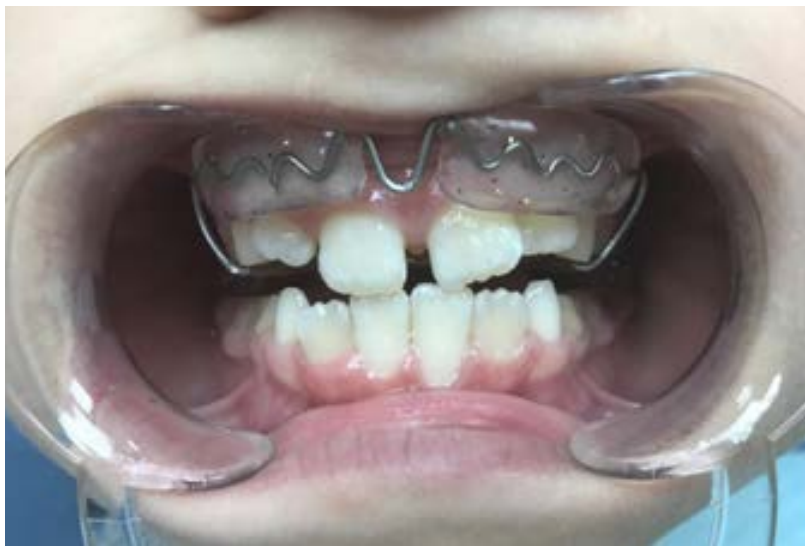

Принятый нами протокол комплексного ортодонтическо-хирургического лечения данной патологии в сменном прикусе заключался:

1. В устранении травмирующего фактора путем разобщения прикуса с помощью съемных ортодонтических устройств (рис. 3);

Рис. 2. ОртопантомограРис. 3. Тот же пациент на этапе ортодонтического лечения: выведение резцов из травмирующего прикуса с помощью ортодонтического устройства — процесс стабилизированмма Ф. А., 10 лет, до лечения